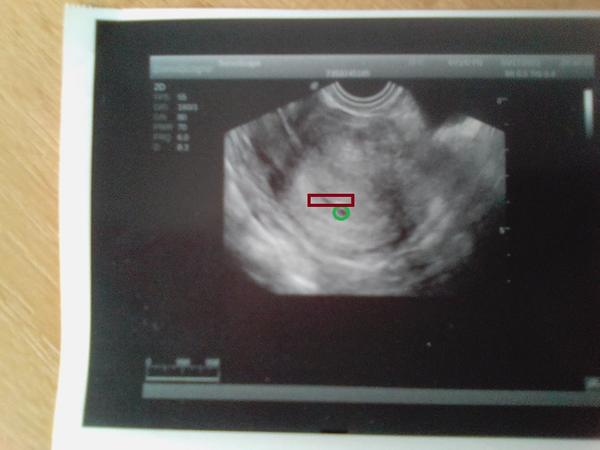

@olcaa jenom tu pidi tečku a nad tou tečkou hematom,tady je to označené.to v zeleném je váček,to v červeném je hematom.

@olcaa ano nic jiného jako embryo neviděl.a nic mi na to neříkal ♥ jen se mu vůbec nelíbil ten hematom,tak jsem vyfasovala hodně léků.pokud praskne,tak mi plod stáhne bohužel sebou.a neboj u třetího jsme měli srdíčko až v 6+3tt,u čtvrtého v 5+6tt